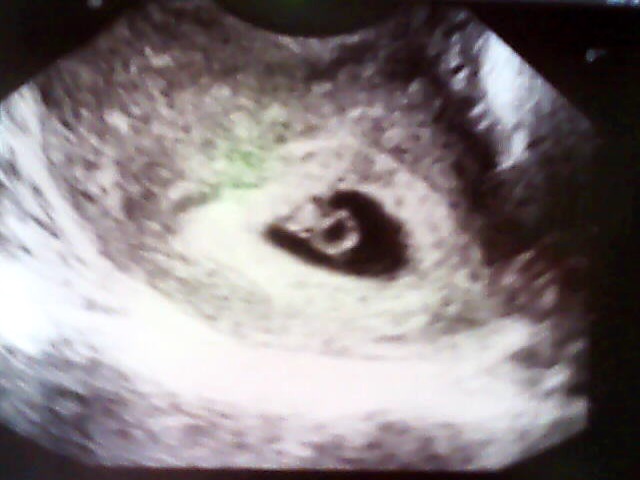

,tak jsem šla za chvíli na wc znova a čárka tam byla,to bylo ve čtvrtek ráno.V sobotu jsem si udělala další test a čárka byla vidět zase o něco lépe,takže jsme letěli v pondělí na gyndu,tam doktorka najela a říká no těhotenství tam je,ale úplně na začátku to byl tak 4 týden a říká za týden na kontrolu,o týden později to jsem byla 5+3 byl už vidět větší gestační váček i se žloutkovým,ale plod ještě vidět nebyl.A ted v pondělí to jsem byla 6+3 už byl vidět jak gestační váček,tak i žloutkový váček a plod se srdíčkem....dám sem všechny tři ultrazvuky at může porovnat jak to rychle roste

a tak ta první to je 4+3 ta druhá vedle ní to je 6+3 a ta spodní v druhém příspěvku je 5+3